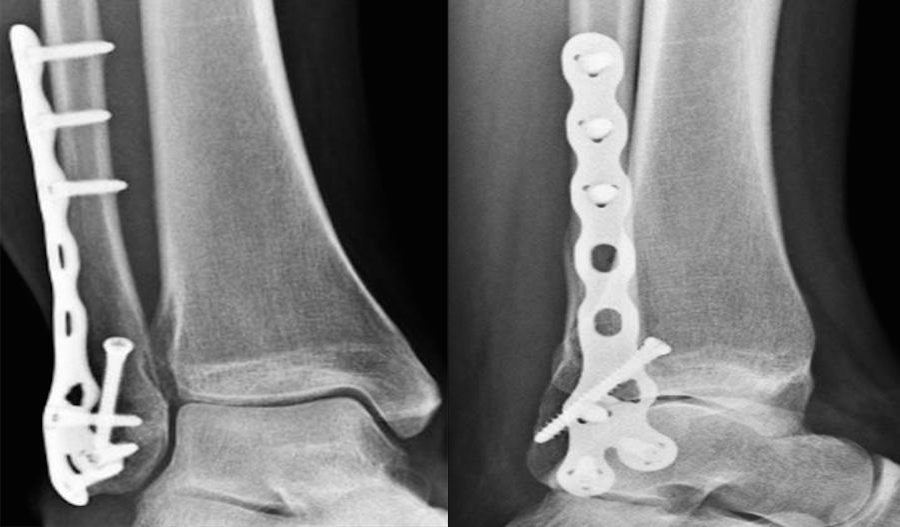

Locking Plate Meaning . locking plates are increasingly being used in the treatment of lateral malleolus fractures. there are two broad categories of locking plates: In poor bone quality and low bone. 방문 중인 사이트에서 설명을 제공하지 않습니다. the advantages of locking plates apply most directly to cases of highly comminuted fractures, unstable metadiaphyseal. Unlike a nail, locking plate is fixed on a bone. Improved stability of fixation/resistance to failure of fixation. What is locking plate and when is it used? advantages of locked plating. the locking plate concept is similar to an external fixator where a threaded screw head is locked in the.